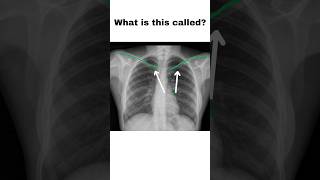

What is this called?👈#radiology #anatomy #ytshorts #medical What is this called? Chest X ray Interpretation 🤔#anatomy #youtube #radiology

What is this called? Chest X ray Interpretation 🤔#anatomy #youtube #radiology What is this called?👈#medical #anatomy #radiology #youtubeshorts

What is this called?🤔#anatomy #radiology #youtubeshorts #xray Chest X-ray Normal vs Abnormal #shorts

Chest X-ray Normal vs Abnormal #shorts Normal lung vs Infected lungs 🫁 #lungs #chest #radiology #xray #neet #radiology #medicos #doctor

Normal lung vs Infected lungs 🫁 #lungs #chest #radiology #xray #neet #radiology #medicos #doctor